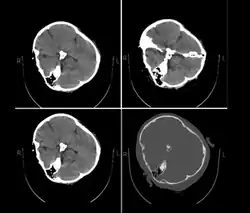

On 16 September 2022, 22-year-old Kurdish-Iranian woman Mahsa Amini,[a] also known as Jina Amini,[b][1][2][3] died in a hospital in Tehran, Iran, under suspicious circumstances. The Guidance Patrol, the religious morality police of Iran's government, had arrested Amini for allegedly not wearing the hijab in accordance with government standards. The Law Enforcement Command of the Islamic Republic of Iran stated that she had a heart attack at a police station, collapsed, and fell into a coma before being transferred to a hospital.[4][5] However, eyewitnesses, including women who were detained with Amini, reported that she was severely beaten and that she died as a result of police brutality,[6][7][8] which was denied by the Iranian authorities.[9] The assertions of police brutality, in addition to leaked medical scans,[10] led some observers to believe Amini had a cerebral hemorrhage or stroke due to head injuries received after her arrest.[11]

Published hospital pictures show Mahsa Amini bleeding from the ear and with bruises under her eyes. In an 18 September letter, Doctor Hossein Karampour (the top medical official in Hormozgan province), pointed out that such symptoms "do not match the reasons given by some authorities who declared the cause to be a heart attack... (they are instead consistent with) a head injury and the resulting bleeding."[76] This was also confirmed by alleged medical scans of her skull, leaked by hacktivists, showing bone fracture, hemorrhage, and brain edema.[10][77]

By 21 September, the hospital had released preliminary CT scans. Government supporters stated the CT scans showed psychological stress caused by a previous brain operation; critics stated the scans showed physical beating and trauma. The Iranian government stated Amini had a brain operation at the age of five.[81]